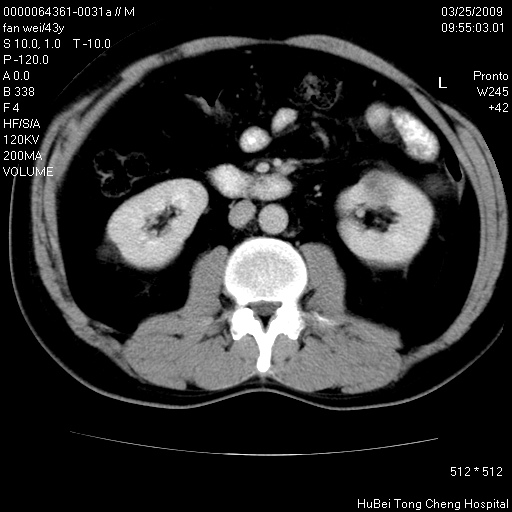

患者 男,43岁。左侧腰部不适两天。平素健康。无家族遗传病史。

腹部彩超提示:1)轻度脂肪肝。2)左肾多发囊性占位性病变;建议行进一步检查。

临床诊断:左肾多发囊性占位性病变,性质待定(多发肾囊肿?)。

双肾ct轴位平扫+增强扫描(层厚10mm,螺距1.0,重建间隔10mm),图像如下:

多囊肾的影像诊断标准:有阳性家族史,年龄<30岁,单侧或双侧肾脏有两个肾囊肿;30~59岁,两侧肾脏各有两个肾囊肿;60岁以上,每侧肾脏有4个囊肿。敏感性和特异性达86%和80%。

此病例影像诊断符合,要结合家族史,腰痛、血尿、尿路感染史,有无高血压等综合判断,如无相应的临床症状,本身病变也无意义了(个人观点)

左肾体积变大,支持多囊肾。

囊肿数得清,肾功能正常,考虑多发肾囊肿.另外,右肾后极突向肾周间隙的那个病灶是不是错构瘤,请楼主调窗看看.